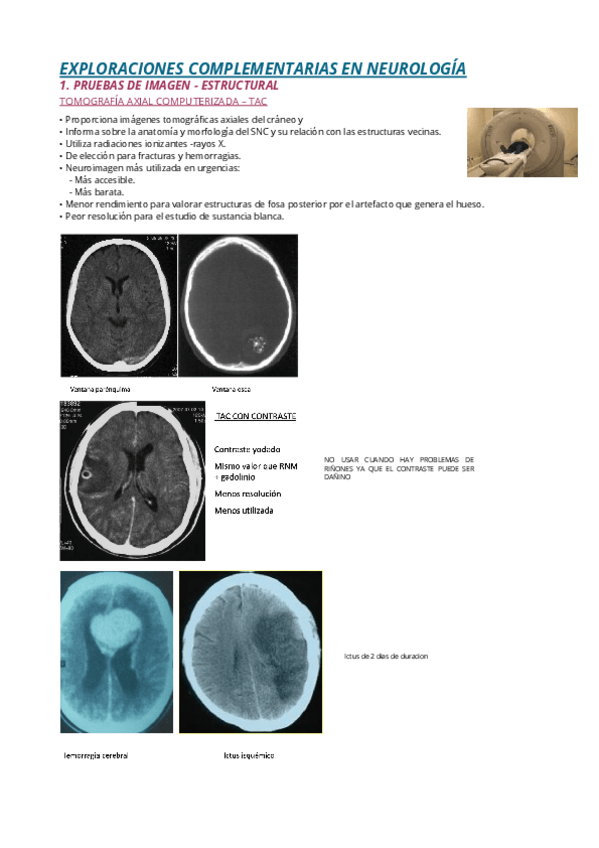

EXPLORACIONES-COMPLEMENTARIAS-EN-NEUROLOGIA.pdf